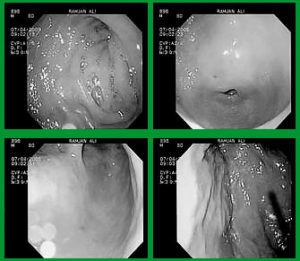

При эндоскопическом обследовании врач видит единичные или множественные сильно гиперемированные участки, на которых почти отсутствует поверхностный эпителий.

- ФГДС – является самым современным методом исследования внутренних органов желудочно-кишечного тракта. Процедура позволяет получить подробную информацию о состоянии слизистой оболочки желудка, сделать фотографии обследуемых участков, осуществить биопсию и взять материал для проведения теста на определение бактерии H. Pylori.

Симптоматика эрозивного гастрита схожа с признаками язвенной болезни. При постановке диагноза, в первую очередь, опираются на результаты ФГДС.

По состоянию поражений определяют, можно ли поставить диагноз эрозивный гастрит. При эндоскопическом исследовании врачи определяют наличие покраснений, отека и кровоточивости слизистой.